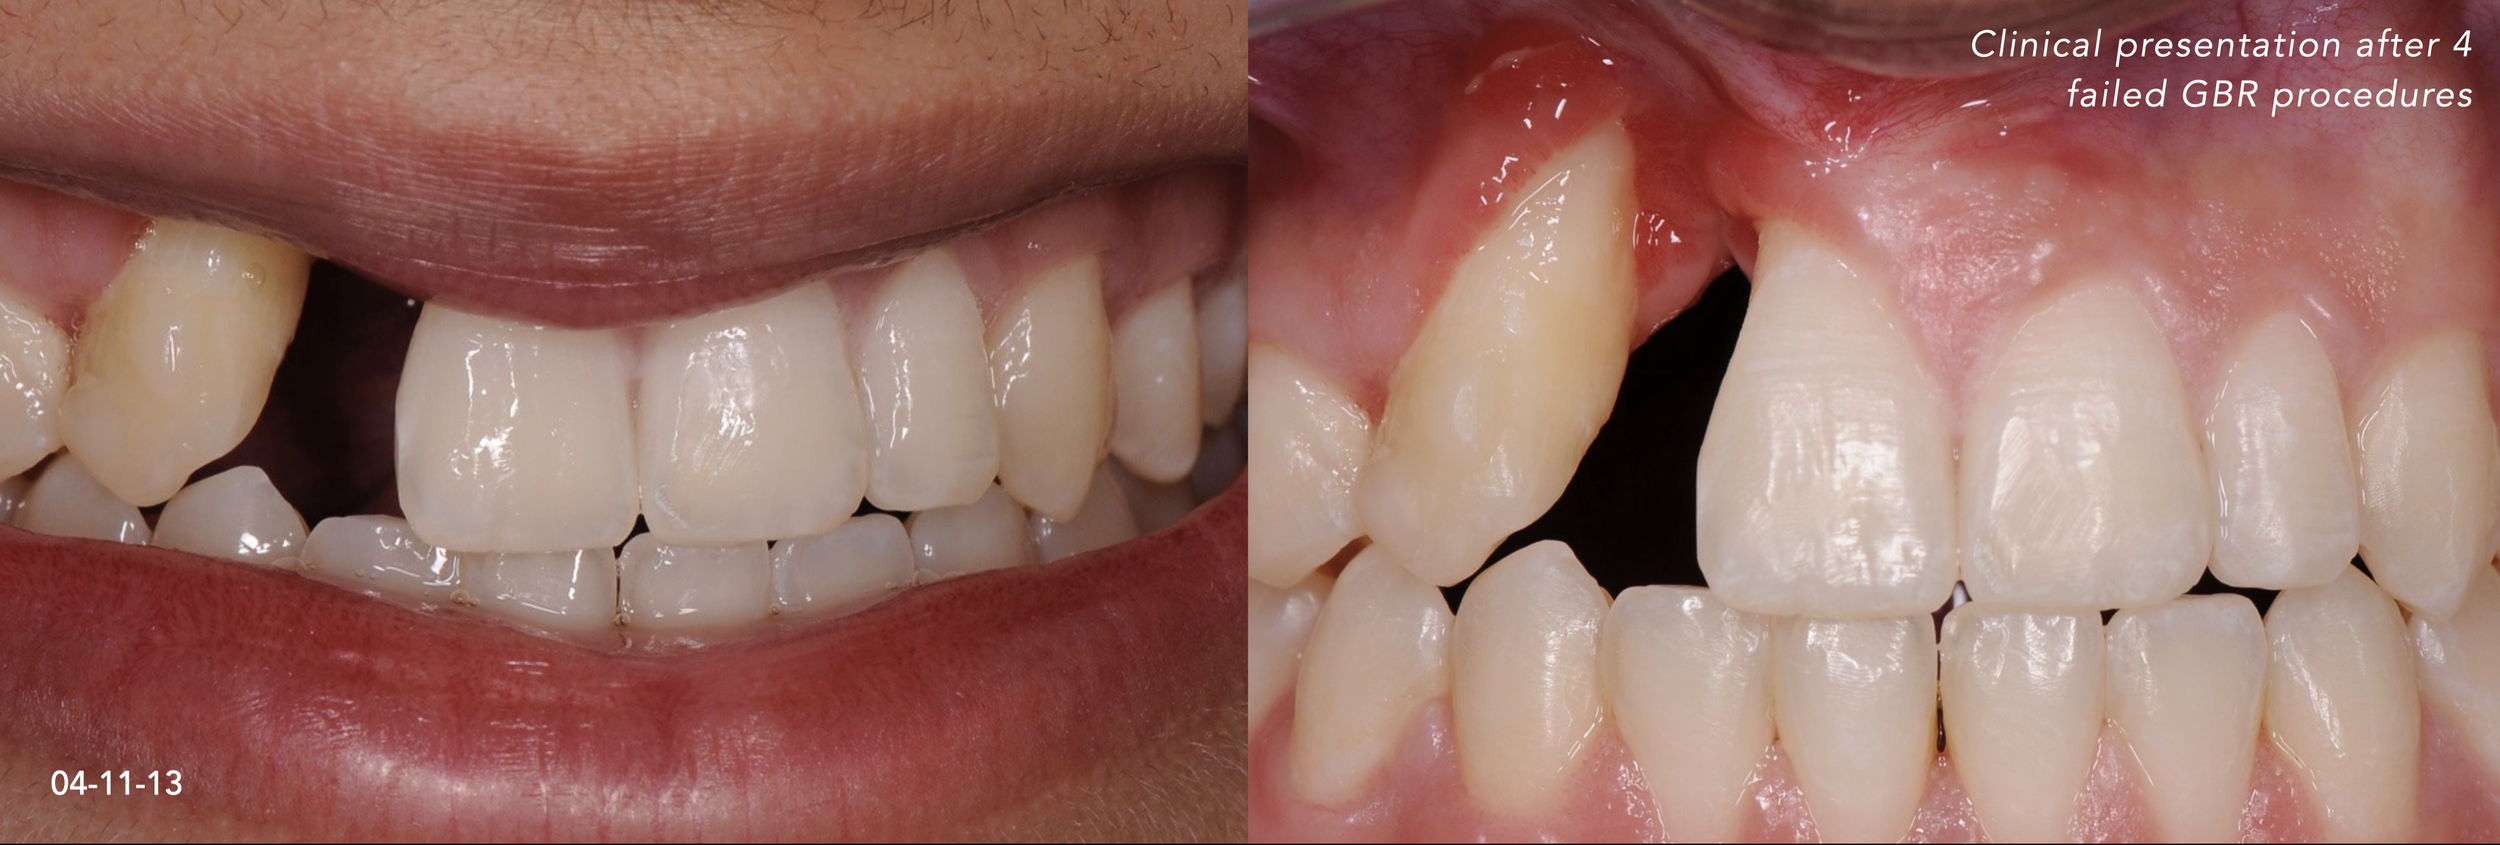

CASE 1. COMPLEX IATROGENIC DEFECT